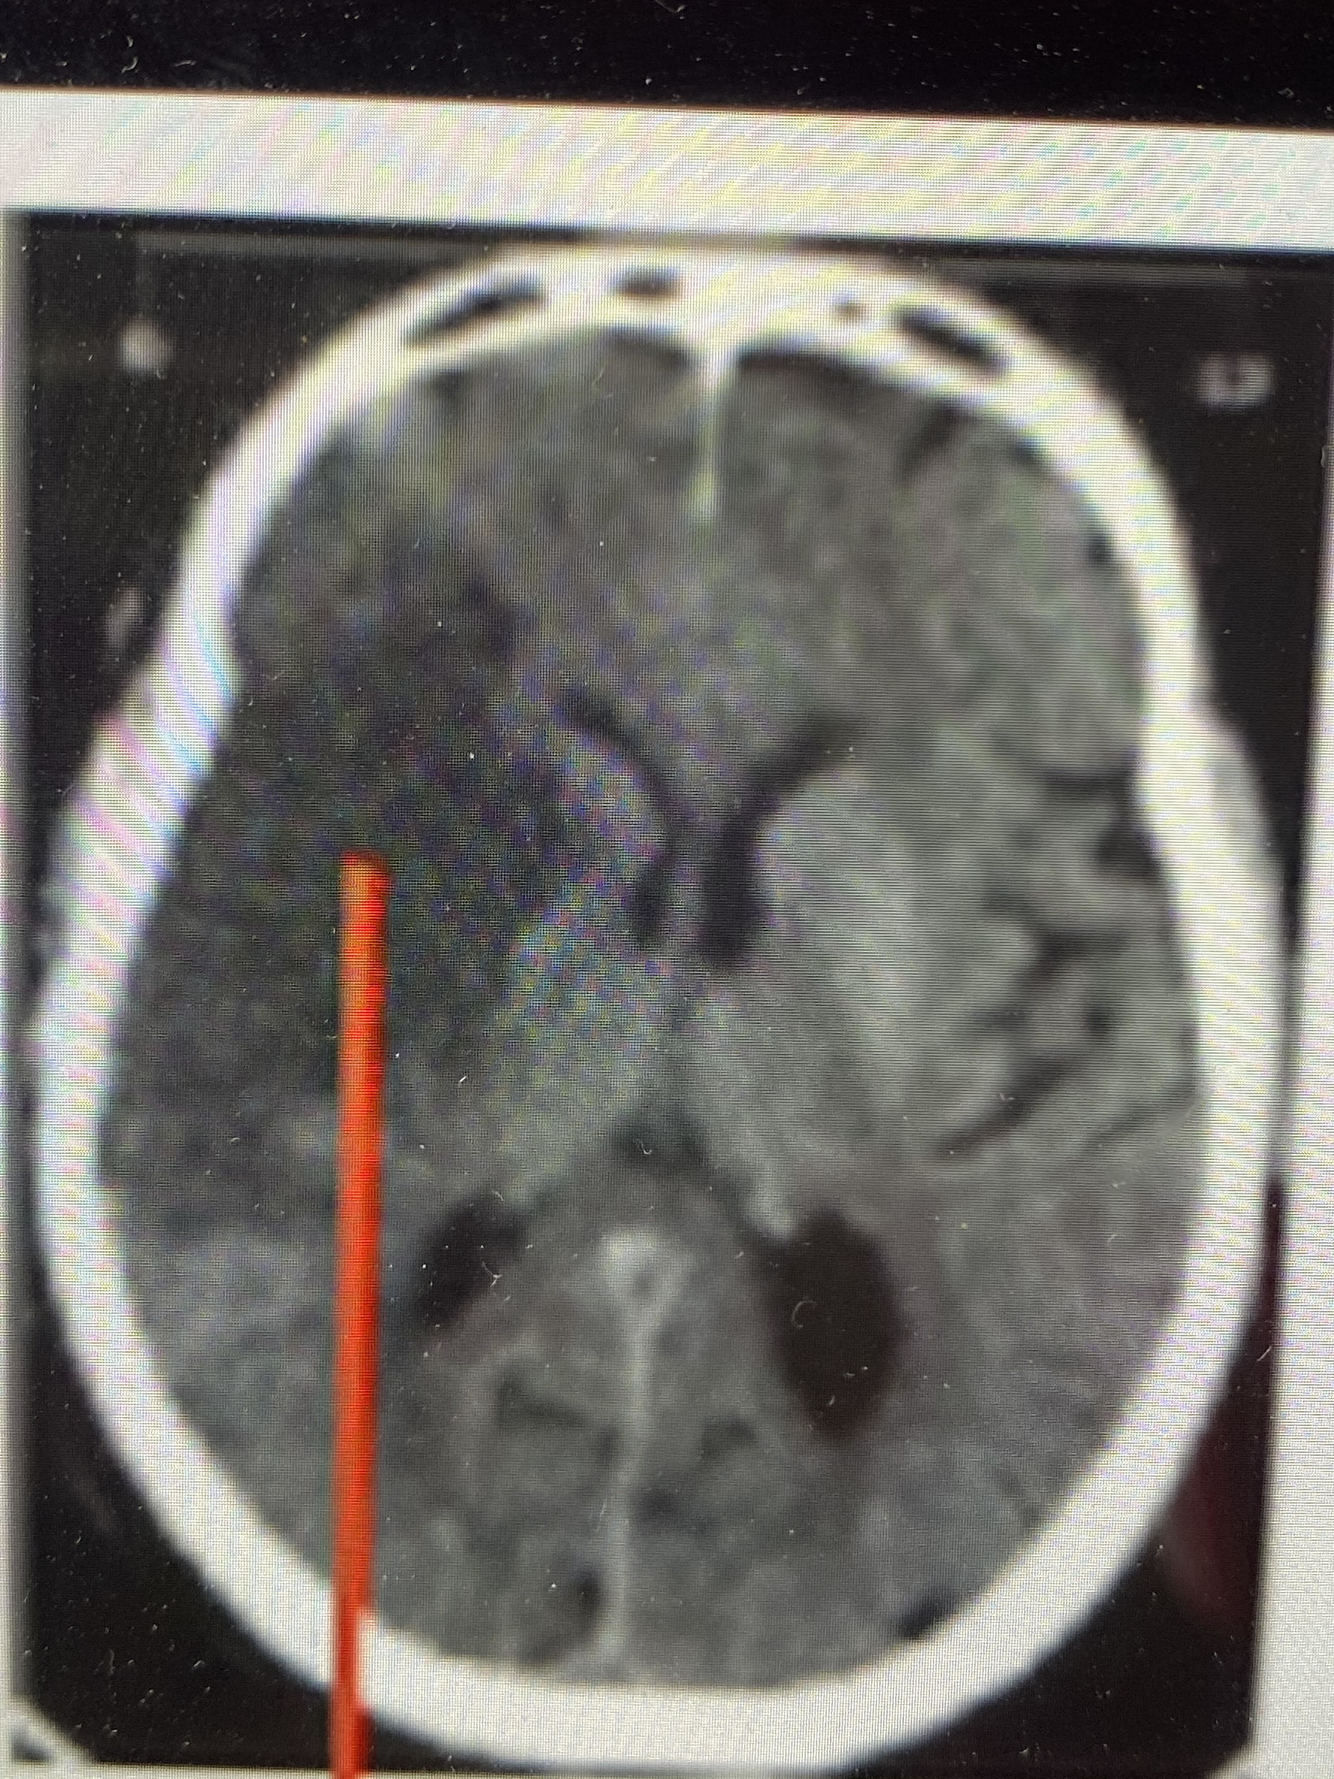

Qual artéria foi afetada?

Cerebral média

Qual Artéria foi acometida nessa imagem?

A. Cerebral Média

(Lateral)